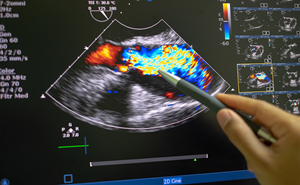

Acute Mitral Regurgitation in the Emergency Department

A 56-year-old female with history of hyperlipidemia, mild mitral regurgitation, and type 2 diabetes presents to the emergency department for 5 days of diffuse chest pain with dyspnea, lower extremity ...